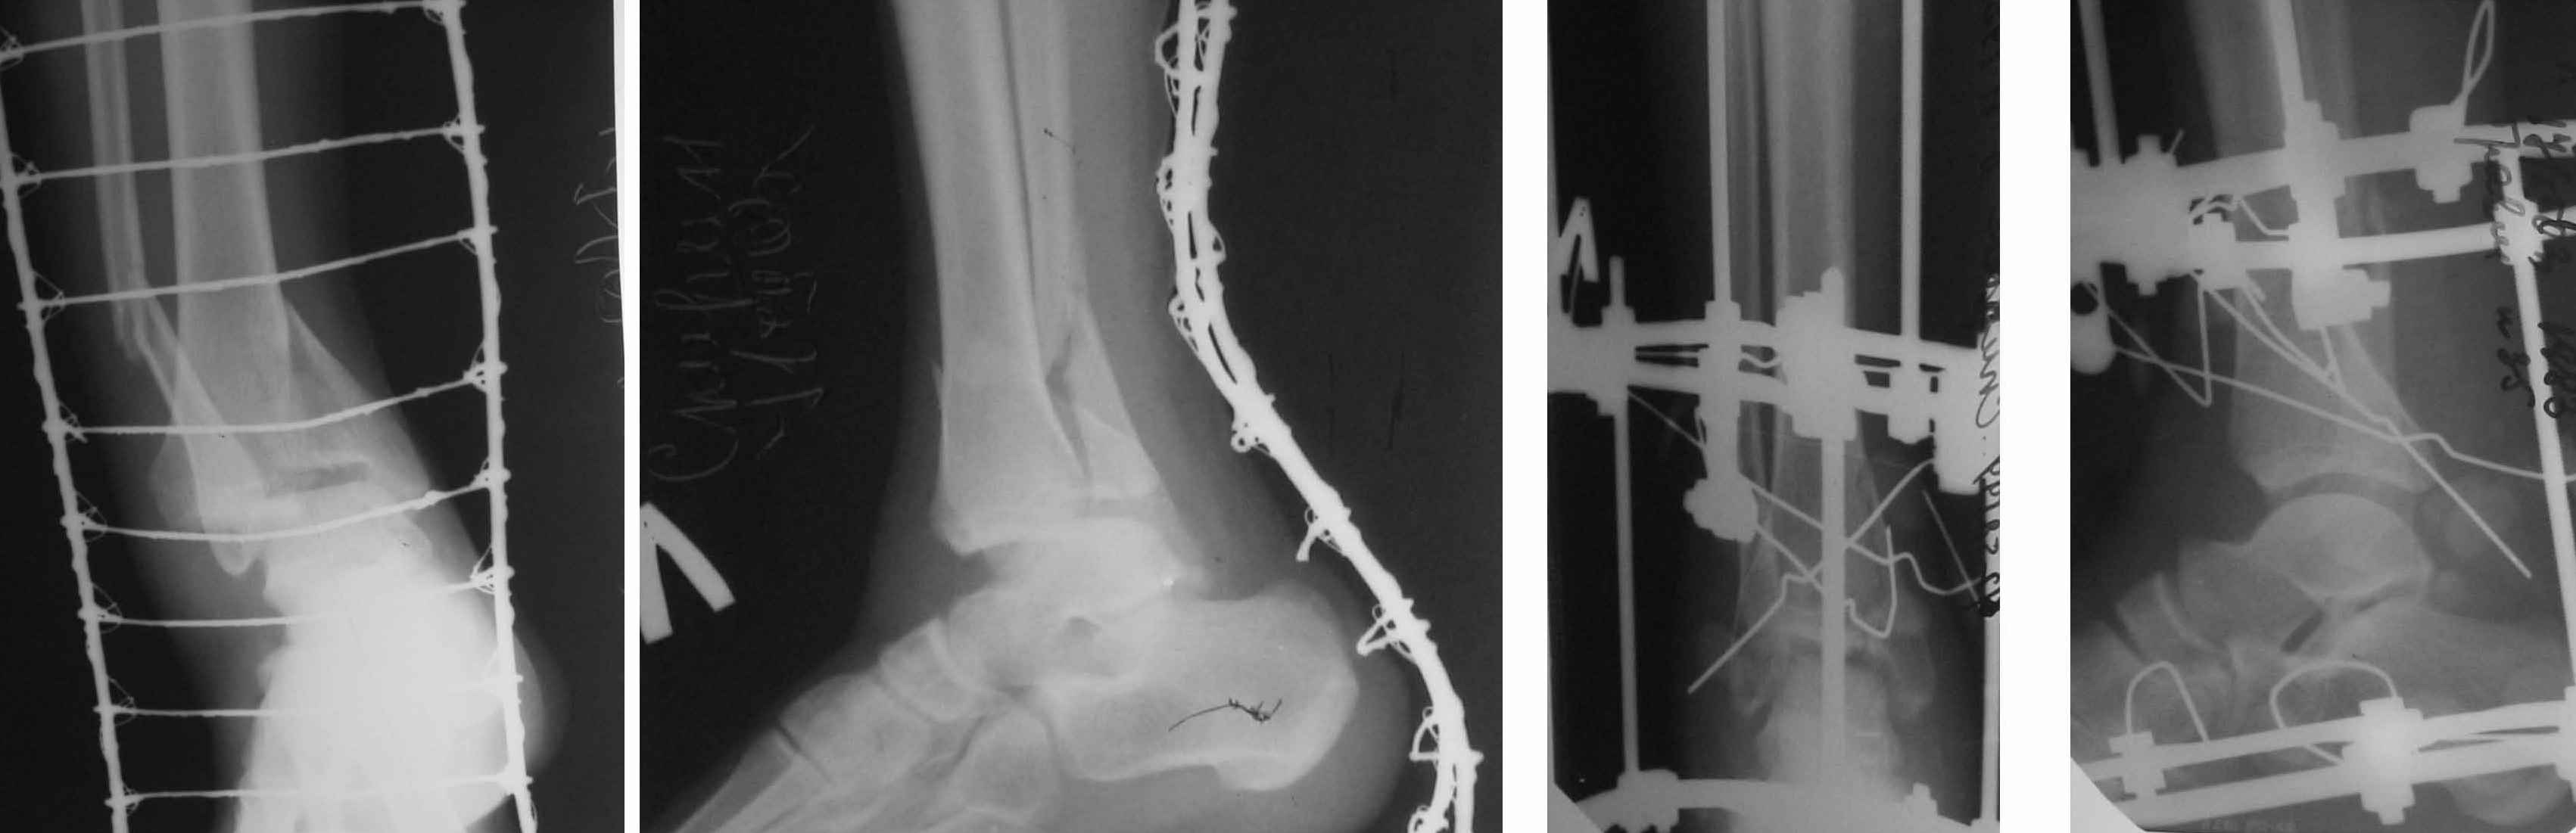

1. Ilizarov frame as definitive managment (it is crucial to perform high-quality about ankle fixation for early distal ring removing and ROM restoration) - see photo.

2. Cross-Ankle external fixation - 1 stage.

After severe soft tissue edema and necrosis resolving - tibial nailing, percutaneous syndesmosis and medial malleolus screw fixation.